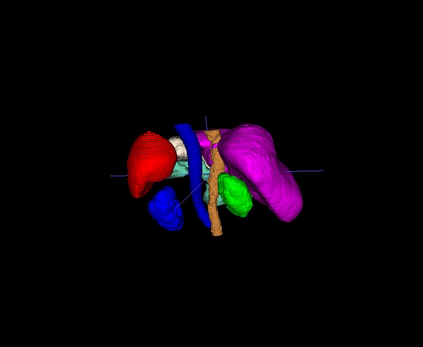

Interactive segmentation, an integration of AI algorithms and human expertise, premises to improve the accuracy and efficiency of curating large-scale, detailed-annotated datasets in healthcare. Human experts revise the annotations predicted by AI, and in turn, AI improves its predictions by learning from these revised annotations. This interactive process continues to enhance the quality of annotations until no major revision is needed from experts. The key challenge is how to leverage AI predicted and expert revised annotations to iteratively improve the AI. Two problems arise: (1) The risk of catastrophic forgetting--the AI tends to forget the previously learned classes if it is only retrained using the expert revised classes. (2) Computational inefficiency when retraining the AI using both AI predicted and expert revised annotations; moreover, given the dominant AI predicted annotations in the dataset, the contribution of newly revised annotations--often account for a very small fraction--to the AI training remains marginal. This paper proposes Continual Tuning to address the problems from two perspectives: network design and data reuse. Firstly, we design a shared network for all classes followed by class-specific networks dedicated to individual classes. To mitigate forgetting, we freeze the shared network for previously learned classes and only update the class-specific network for revised classes. Secondly, we reuse a small fraction of data with previous annotations to avoid over-computing. The selection of such data relies on the importance estimate of each data. The importance score is computed by combining the uncertainty and consistency of AI predictions. Our experiments demonstrate that Continual Tuning achieves a speed 16x greater than repeatedly training AI from scratch without compromising the performance.